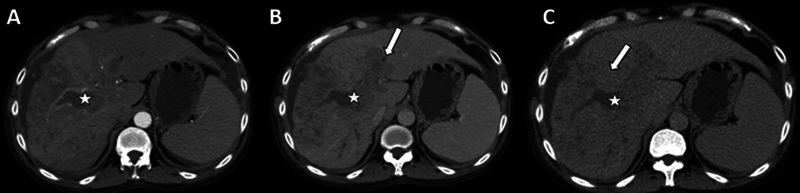

目的比较浸润性肝细胞癌(HCC)与结节性肝细胞癌(结节性肝癌)的多期增强ct (CECT)特征,评价浸润性肝细胞癌不同期CECT的显著性。材料和方法本回顾性研究纳入了2020年1月至2021年12月期间诊断为浸润性和结节性HCC的连续未接受治疗的肝硬化患者,基于多期CECT(包括动脉期、门静脉期和延迟期)。HCC的诊断依据肝成像报告和数据系统(LI-RADS) v2018标准(LR-4和LR-5病变)。浸润性hcc的特征是大的、不规则的、浸润性病变,分布在多个肝节段或肝叶。结节性hcc包括定义明确的肿瘤结节。两名放射科医生独立审查了所有CT图像。此外,还评估了动脉、门静脉和延迟期病变的显著性。结果158例患者中,结节性hcc 117例,浸润性hcc 41例;平均年龄:55.6±17.2岁;包括90例(56.9%)男性。动脉期高强化、门静脉/延迟期冲洗、延迟期增强胶囊与结节性hcc有显著相关性(p = 0.002、0.0001、p)。结论浸润性hcc与结节性hcc相比,主要LI-RADS表现较少,静脉血栓形成是诊断的重要线索。多相CECT的延迟期是识别这些病变的关键。

Objective  The aims of this study are to compare the multiphasic contrast-enhanced computed tomography (CECT) characteristics of infiltrative hepatocellular carcinoma (HCC) with nodular HCC and to assess the conspicuity of infiltrative HCC on different phases of CECT. Materials and Methods  This retrospective study comprised consecutive treatment-naive cirrhotic patients diagnosed with infiltrative and nodular HCC between January 2020 and December 2021 based on a multiphasic CECT (comprising arterial, portal venous, and delayed phases). The diagnosis of HCC was based on the Liver Imaging Reporting and Data System (LI-RADS) v2018 criteria (LR-4 and LR-5 lesions). Infiltrative HCCs are characterized by large, irregular, permeative lesions spread over multiple liver segments or lobes. Nodular HCCs comprise well-defined tumor nodules. Two radiologists independently reviewed all CT images. Additionally, lesion conspicuity on the arterial, portal venous, and delayed phases was assessed. Results  One hundred fifty-eight patients (117 nodular and 41 infiltrative HCCs; mean age: 55.6 ± 17.2 years; 90 [56.9%] males) were included. Arterial phase hyperenhancement, portal venous/delayed phase washout, and delayed phase enhancing capsule were significantly associated with nodular HCCs ( p  = 0.002, 0.0001, and <0.0001, respectively). Portal vein, hepatic vein thrombosis, biliary dilatation, and ascites were significantly associated with infiltrative HCCs ( p  < 0.0001, 0.004, <0.0001, and 0.003, respectively). The interobserver agreement for the conspicuity of infiltrative HCC was the highest for the delayed phase (weighted kappa = 0.611). Conclusion  Infiltrative HCCs show the major LI-RADS features less frequently compared with nodular HCCs, and venous thrombosis is an important clue to the diagnosis. The delayed phase of multiphasic CECT is critical to identifying these lesions.